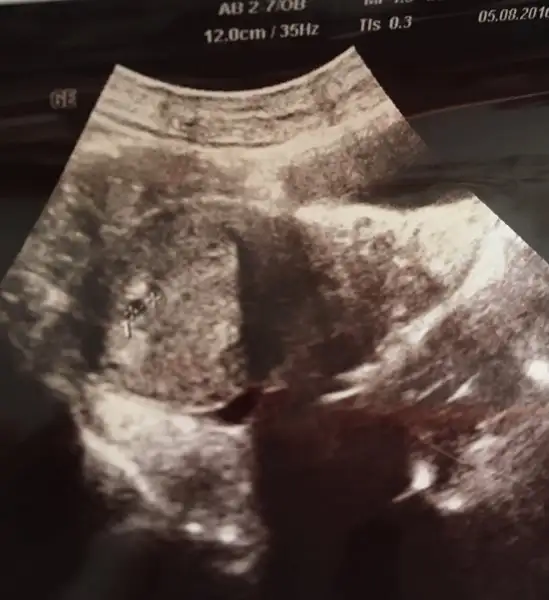

4,84 mm bebişin büyüklüğü benimki de 3,3 mm oluyo işte :)Arkdslar bu benim ultrasyon görüntüm bu ne anlama geliyor şimdi :/ bide 4.84mm yazıoyor

Zaten normalde tek kese tek kararti oluyor cnm bir de ben de unutmuşum hep o ultrason resmindeki değerlerin bir anlamı vardı biri baş biri boy biri kesenin uzunluguydu FL diye bir değer vardı o 7 ile carpilinca çocuğun boyunun uzunluğu bulunuyordu hepsini unutmuşum tekrar en baştan yaşamak çok güzel :)Ya sende sanki iki tane karartı var benimkinde bir tane neden acaba

Kuzum ben hiç anlamıyorum kiYa sende sanki iki tane karartı var benimkinde bir tane neden acaba

Kesenin büyüklüğü o4,84 mm bebişin büyüklüğü benimki de 3,3 mm oluyo işte :)

Nerde 2 karartı. İkiz mi yoksaAyy normal mi diyosunz yani çok sağol ya bi içim rahatladı yani :) ya ne bilim onda iki görününce bende mi bi anormallik var acaba dedim . Neyse çok şükür . Ay o değerlerin ne olduğunu öğrenemk lazım o zaman yaa

Hayır bebeğin olduğu kısmı işaretledi o sayı çıktı. Keseyi ölçmedikiKesenin büyüklüğü o